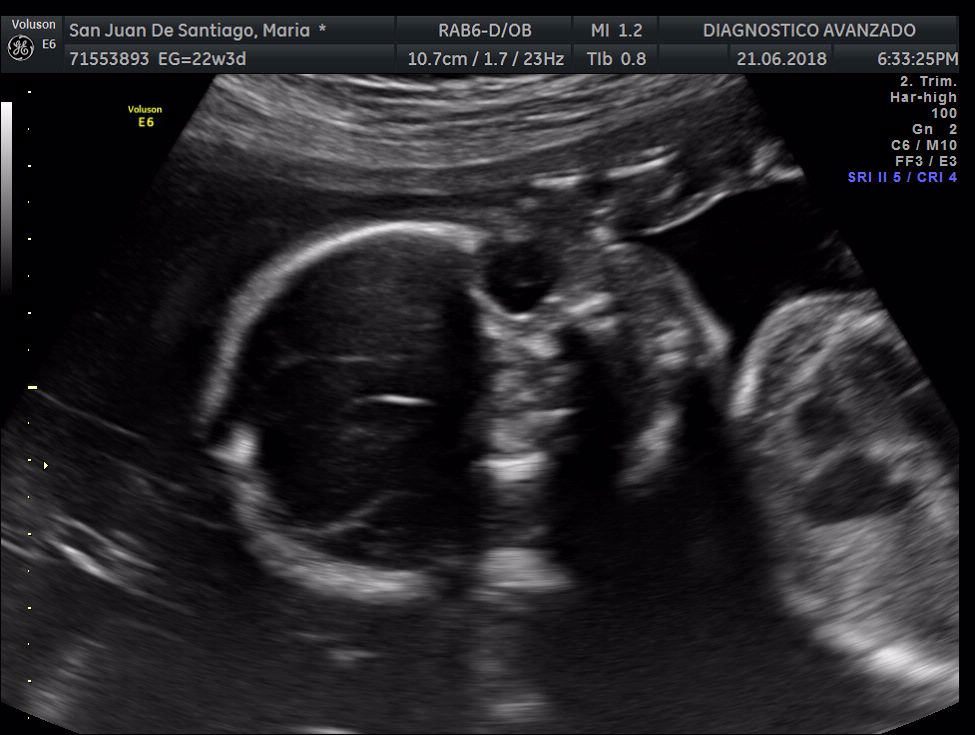

¡Hola a todos! Hoy hemos ido a hacer la tradicional ecografía 3D de la niña, os dejamos todo el material (aunque es un poco demasiado).